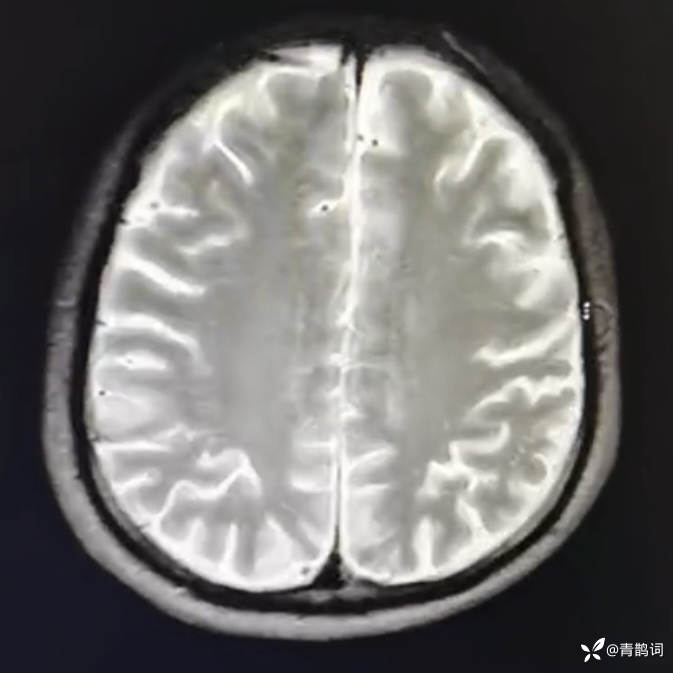

乐痴于医等 2人推荐简要病史:42岁男性,记忆力下降及听力下降一年余。既往体健,否认前驱感染病史。否认家族史。三个月前就诊于当地医院,自述腰穿脑脊液乳酸增高。现就诊于我院,查体记忆力下降,计算力下降,定时定向差,吟诗样语言。完善磁共振如下:

T2: